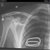

Qualche ora dopo, davanti ad una radiografia... **MESI DI RIPOSO !!! morfina, una prescrizione per essere operato e un bel tutore**, mi sono reso conto (per l'ennesima volta) che non siamo di gomma, e gli errori li paghiamo.

Infermiera "Vieni che ti accompagno in sala RX, poi potrai andare a casa"

Chirurgo " Le RX post operatorio SPACCANO, in meno di 2 MESI ti togliamo tutto e torni quasi come nuovo, devi solo far attenzione a non [...]"

Ortopedico "L'RX mostra un buon allineamento, le consiglio di restare a riposo ancora un paio di mesi prima di tornare a sollevare eventuali pesi"